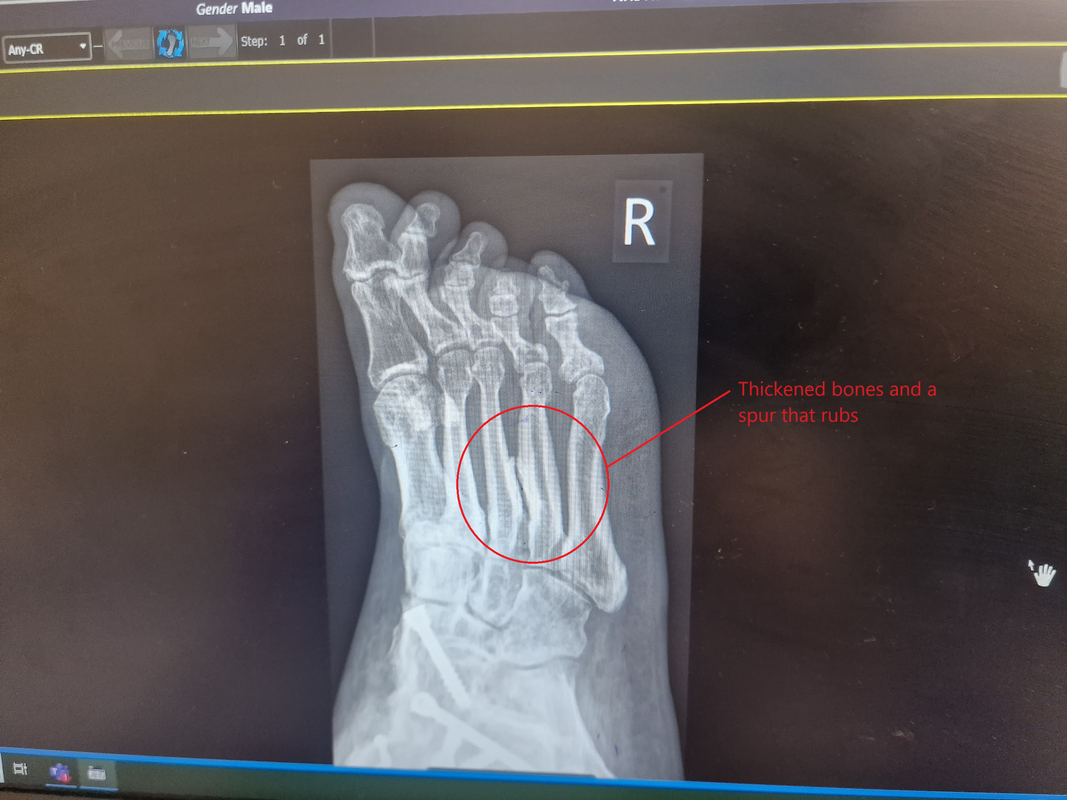

I am actually feeling okay at the moment as I had an injection in my right foot to reduce the pain where the bones rub on Tuesday. As that has removed the pain, but only temporarily, they are probably going to dremel off the offending bits of bone in the coming months. Hopefully this will give me a more permanent, well a few years, of pain relief for this bit. The TENS machine works really well on the persistent ankle pain so I am almost pain free in the right leg for the first time in ten years since I snapped the foot off.

I know you all love my injury pictures so here is the latest x-ray.